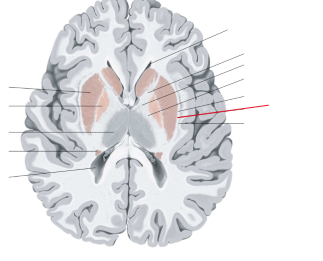

nucleus caudatus

putamen

globus pallidus

capsula interna (corona radiata)

capsula externa

capsula extrema

laterale ventrikels (I en II)